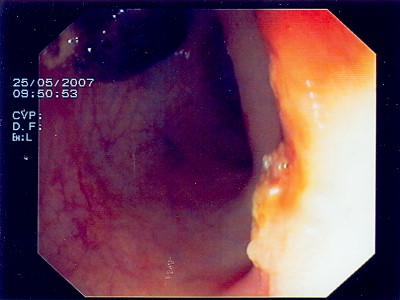

Gut sichtbarer Blutstrahl nach Abtragung eines Polypen

Sichere Blutstillung durch einen Metallclip